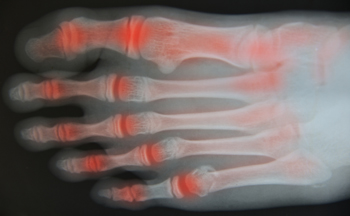

Rheumatoid Arthritis (RA) is an autoimmune disorder in which the body’s own immune system attacks the membranes surrounding the joints. Inflammation of the lining and eventually the destruction of the joint’s cartilage and bone occur, causing severe pain and immobility.

Rheumatoid Arthritis of the Feet

Although RA usually attacks multiple bones and joints throughout the entire body, almost 90 percent of cases result in pain in the foot or ankle area.

- Swelling and pain in the feet

- Stiffness in the feet

- Pain on the ball or sole of feet

- Joint shift and deformation